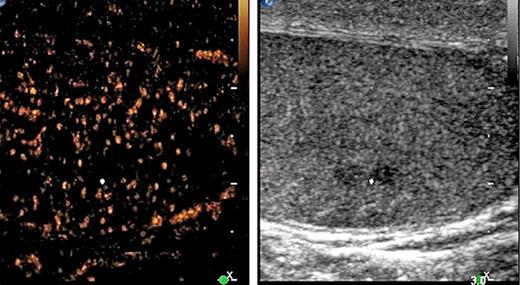

4th patient: this 37-year-old patient had left-sided orchiectomy for a presumed occult germ cell tumour. Histologically, only germ cell neoplasia in situ (TNM: pTis) was found in the specimen. CT revealed a 1.8 cm lymphadenopathy in the para-aortal template. All of the classical serum tumour markers were negative. As histopathologically no invasive GCT was found in the left orchiectomy specimen, the lymphadenopathy was considered unspecific corresponding to a CS1. Accordingly, the patient was put on a surveillance schedule. Four months later, the lymphadenopathy had slightly increased (Fig. 3). Therefore, a laparoscopic lymphadenectomy was performed. Histologically, the specimen revealed a pure seminomatous metastasis. The patient received 3 cycles of BEP chemotherapy subsequently. Before orchiectomy, the miR371a-3p serum level was RQ = 74.4 and it was found to decrease to RQ = 20.4 three days postoperatively, thus clearly lying in the supra-normal range. Prior to lymphadenectomy, the level had increased to RQ = 58.5 and it dropped to RQ = 0.0 after surgical excision of the node to remain there during the later course.